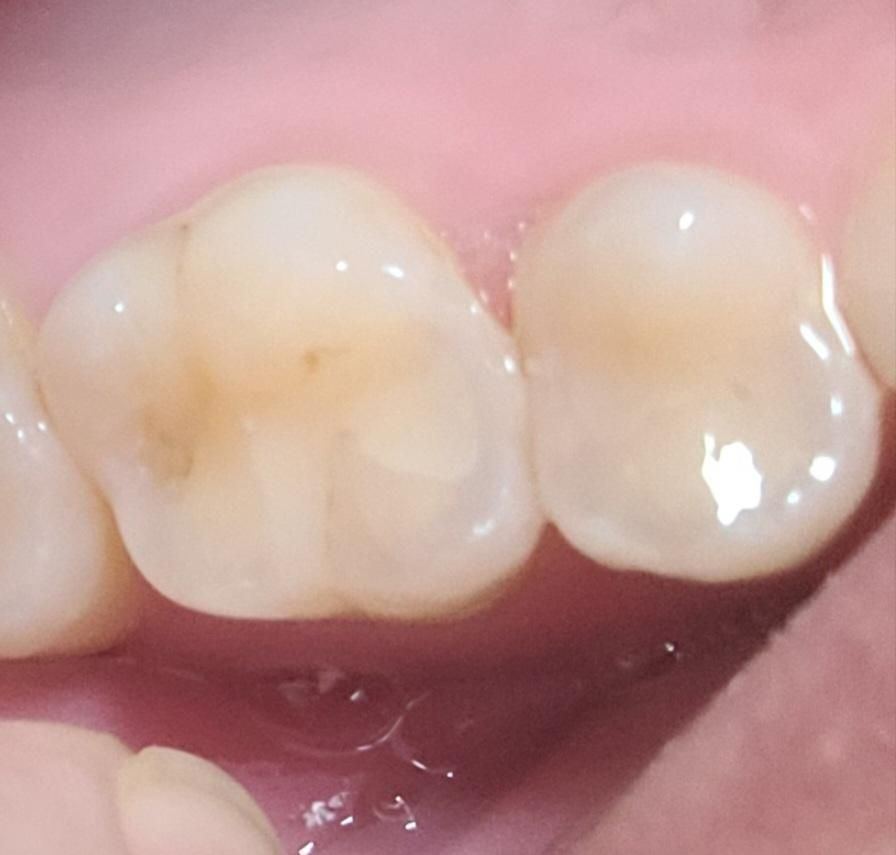

소구치와 대구치 사이가 까맣게 보여요.충치일까요?

제가 양치하고 치아를 살펴보니 소구치와 대구치 사이가 까맣게 보였습니다.

하지만 그 치아들은 9월에 레진치료를 받았고 10월에 충치확인을 위해 병원갔을 때도 별다른 이야기가 없었습니다. 하지만 그때 전체로 찍은 사진만 보셔서 조금 불안합니다.

• 4번 째 사진

약간 충치의 가능성도 있어보이지만 치아 사이는 엑스레이를 통해서 확인해보는 것이 좋습니다.

육안상으로는 충치가 아닐꺼 같긴합니다. 정확한건 치과에 가셔서 엑스레이를 찍어보셔야될것같습니다.